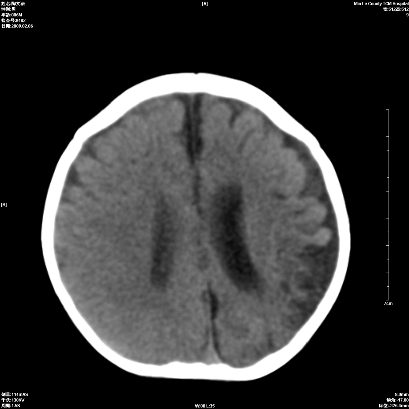

以下是引用wxq2008在2009-2-6 17:01:00的发言:[br]hie后遗症脑萎缩。

以下是引用学医在2009-2-6 21:45:00的发言:[br]hie后遗改变